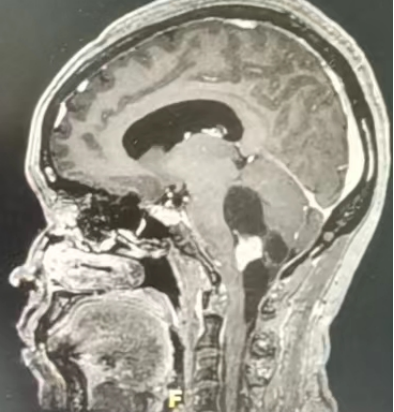

病情介紹:王某 女 70歲頭暈、伴走路不穩(wěn)半年,加重1周。既往身體健康。入院半年前無明顯誘因開始出現(xiàn)頭暈、惡心癥狀,偶有嘔吐,走路時(shí)易向左側(cè)傾倒,開始未在意,近1周癥狀明顯加重,左手持物不穩(wěn),無法自行走路。就診于當(dāng)?shù)蒯t(yī)院行頭CT檢查發(fā)現(xiàn)左小腦半球占位性病變。為求手術(shù)治療來我院。入院查體:左側(cè)肢體共濟(jì)失調(diào),走路不能呈直線,向左側(cè)傾倒,左手指鼻試驗(yàn)欠穩(wěn)準(zhǔn)。術(shù)前核磁共振檢查入院后完善頭部核磁共振檢查,結(jié)果提示左小腦半球占位性病變,符合典型血管母細(xì)胞瘤影像特點(diǎn)。治療經(jīng)過:入院后完善術(shù)前常規(guī)檢查無手術(shù)禁忌,術(shù)前診斷左小腦半球血管母細(xì)胞瘤,手術(shù)指征明確。擇期全麻下行左枕下開顱、左小腦半球血管母細(xì)胞瘤切除術(shù)。術(shù)中全切腫瘤。術(shù)后病理結(jié)果回報(bào)血管母細(xì)胞瘤?;颊咝g(shù)后痊愈出院。術(shù)后情況術(shù)后第3天復(fù)查頭部增強(qiáng)磁共振示:腫瘤全切除,占位完全緩解。出院情況:患者出院時(shí)左側(cè)肢體共濟(jì)失調(diào)癥狀明顯改善,可自行行走。血管母細(xì)胞瘤小科普血管母細(xì)胞瘤為血管周圍間葉組織起源的良性腫瘤,大多數(shù)血管母細(xì)胞瘤為偶發(fā)的單一病灶。極少數(shù)的血管母細(xì)胞瘤出現(xiàn)在一種所謂“vonHippelLindau”(VHL)疾病的病患身上,該病具有遺傳性,血管母細(xì)胞瘤是這個(gè)基因癥候群的一種表現(xiàn),患病者終其一生會(huì)在他們的腦和脊髓里出現(xiàn)許多的腫瘤。幾乎所有病灶都發(fā)生小腦半球。而小腦在腦部的主要功能是平衡和協(xié)調(diào)。血管母細(xì)胞瘤會(huì)有兩種基本的形態(tài),包括囊性和實(shí)性。實(shí)性腫瘤幾乎全部由細(xì)胞所組成,而囊性腫瘤則是小部分的細(xì)胞伴隨著大部分的囊泡所組成的。隨著血管母細(xì)胞瘤的生長(zhǎng),日益增大的腫瘤將會(huì)壓迫到腦部,并且造成一些神經(jīng)學(xué)上的癥狀,例如頭痛、肢體無力、感覺喪失、平衡和協(xié)調(diào)問題,或是腦積水。在一些少見的病例中,這種腫瘤會(huì)由于一些和神經(jīng)學(xué)不相關(guān)的癥狀或是疾病,而無意中被發(fā)現(xiàn)。血管母細(xì)胞瘤可以選擇兩種基本的治療方法。第一種是開刀將影響到腦的腫瘤切除掉。如果病患的血管母細(xì)胞瘤可以完全切除,而且在疾病分類上不是屬于von Hippel Lindau的話,這個(gè)病患就算是治愈了。 在一些典型囊泡狀血管母細(xì)胞瘤的病患中,只有實(shí)性腫瘤的部分是需要移除掉,至於囊泡狀腫瘤的部分,則是在手術(shù)中引流出來,而且這囊泡將會(huì)在腫瘤被移除後消失。假如血管母細(xì)胞瘤無法全部切除,腫瘤有可能會(huì)重新生長(zhǎng)或是會(huì)有更多的囊泡產(chǎn)生。任何腦部的手術(shù)都是具有侵入性的,并且有一定風(fēng)險(xiǎn),例如出血、感染、麻醉并發(fā)癥或是神經(jīng)功能的缺損。盡管如此,隨著現(xiàn)代神經(jīng)外科手術(shù)技術(shù)、設(shè)備及精準(zhǔn)理念的飛速發(fā)展,手術(shù)安全性和有效性大大提高,大多數(shù)的血管母細(xì)胞瘤是可以安全手術(shù)移除的。相對(duì)于開顱手術(shù),立體定位放射線治療可以用來定位和破壞血管母細(xì)胞瘤。單一劑量的放射線治療會(huì)造成細(xì)胞逐漸死亡,然後細(xì)胞自然萎縮。在血管母細(xì)胞瘤的病患中,只有實(shí)性腫瘤的部分是需要用放射線治療來消除的;囊液會(huì)慢慢地減少產(chǎn)生,最後囊泡會(huì)逐漸變小。放射治療尤其適用于腫瘤體積較小或高齡不能耐受手術(shù)患者。